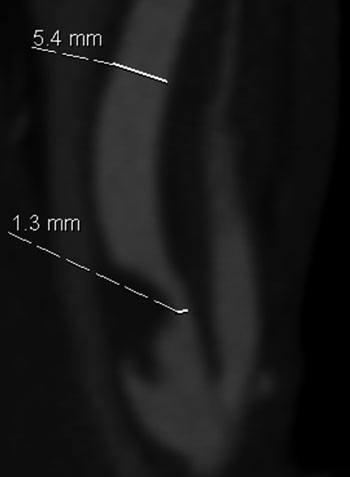

I de senere år har utvikling av MR- og CT-teknologi gitt nye muligheter for ikke-invasiv diagnostikk. CT-angiografi med moderne 64-kanalers spiral-CT gir detaljerte bilder av stenosen og forandringene i karveggen som tromber og kalk, og man får i samme skanning fremstilling av hele forløpet fra aortabuen til intracerebrale kar. Dette er nyttig i forhold til å vurdere egnethet for kirurgi eller stentbehandling. Hos oss henvises nå til ultralydundersøkelse av halskar som første screening, og CT-angiografi gjøres deretter som ledd i preoperativ planlegging. Vi benytter de aksiale originalsnittene til å måle karlumen og visualisere kalk, tromber og ulcerasjoner, for så ved hjelp av koronale og sagittale rekonstruksjoner å beregne stenosegrad på samme måte som ved konvensjonell angiografi (fig 3).